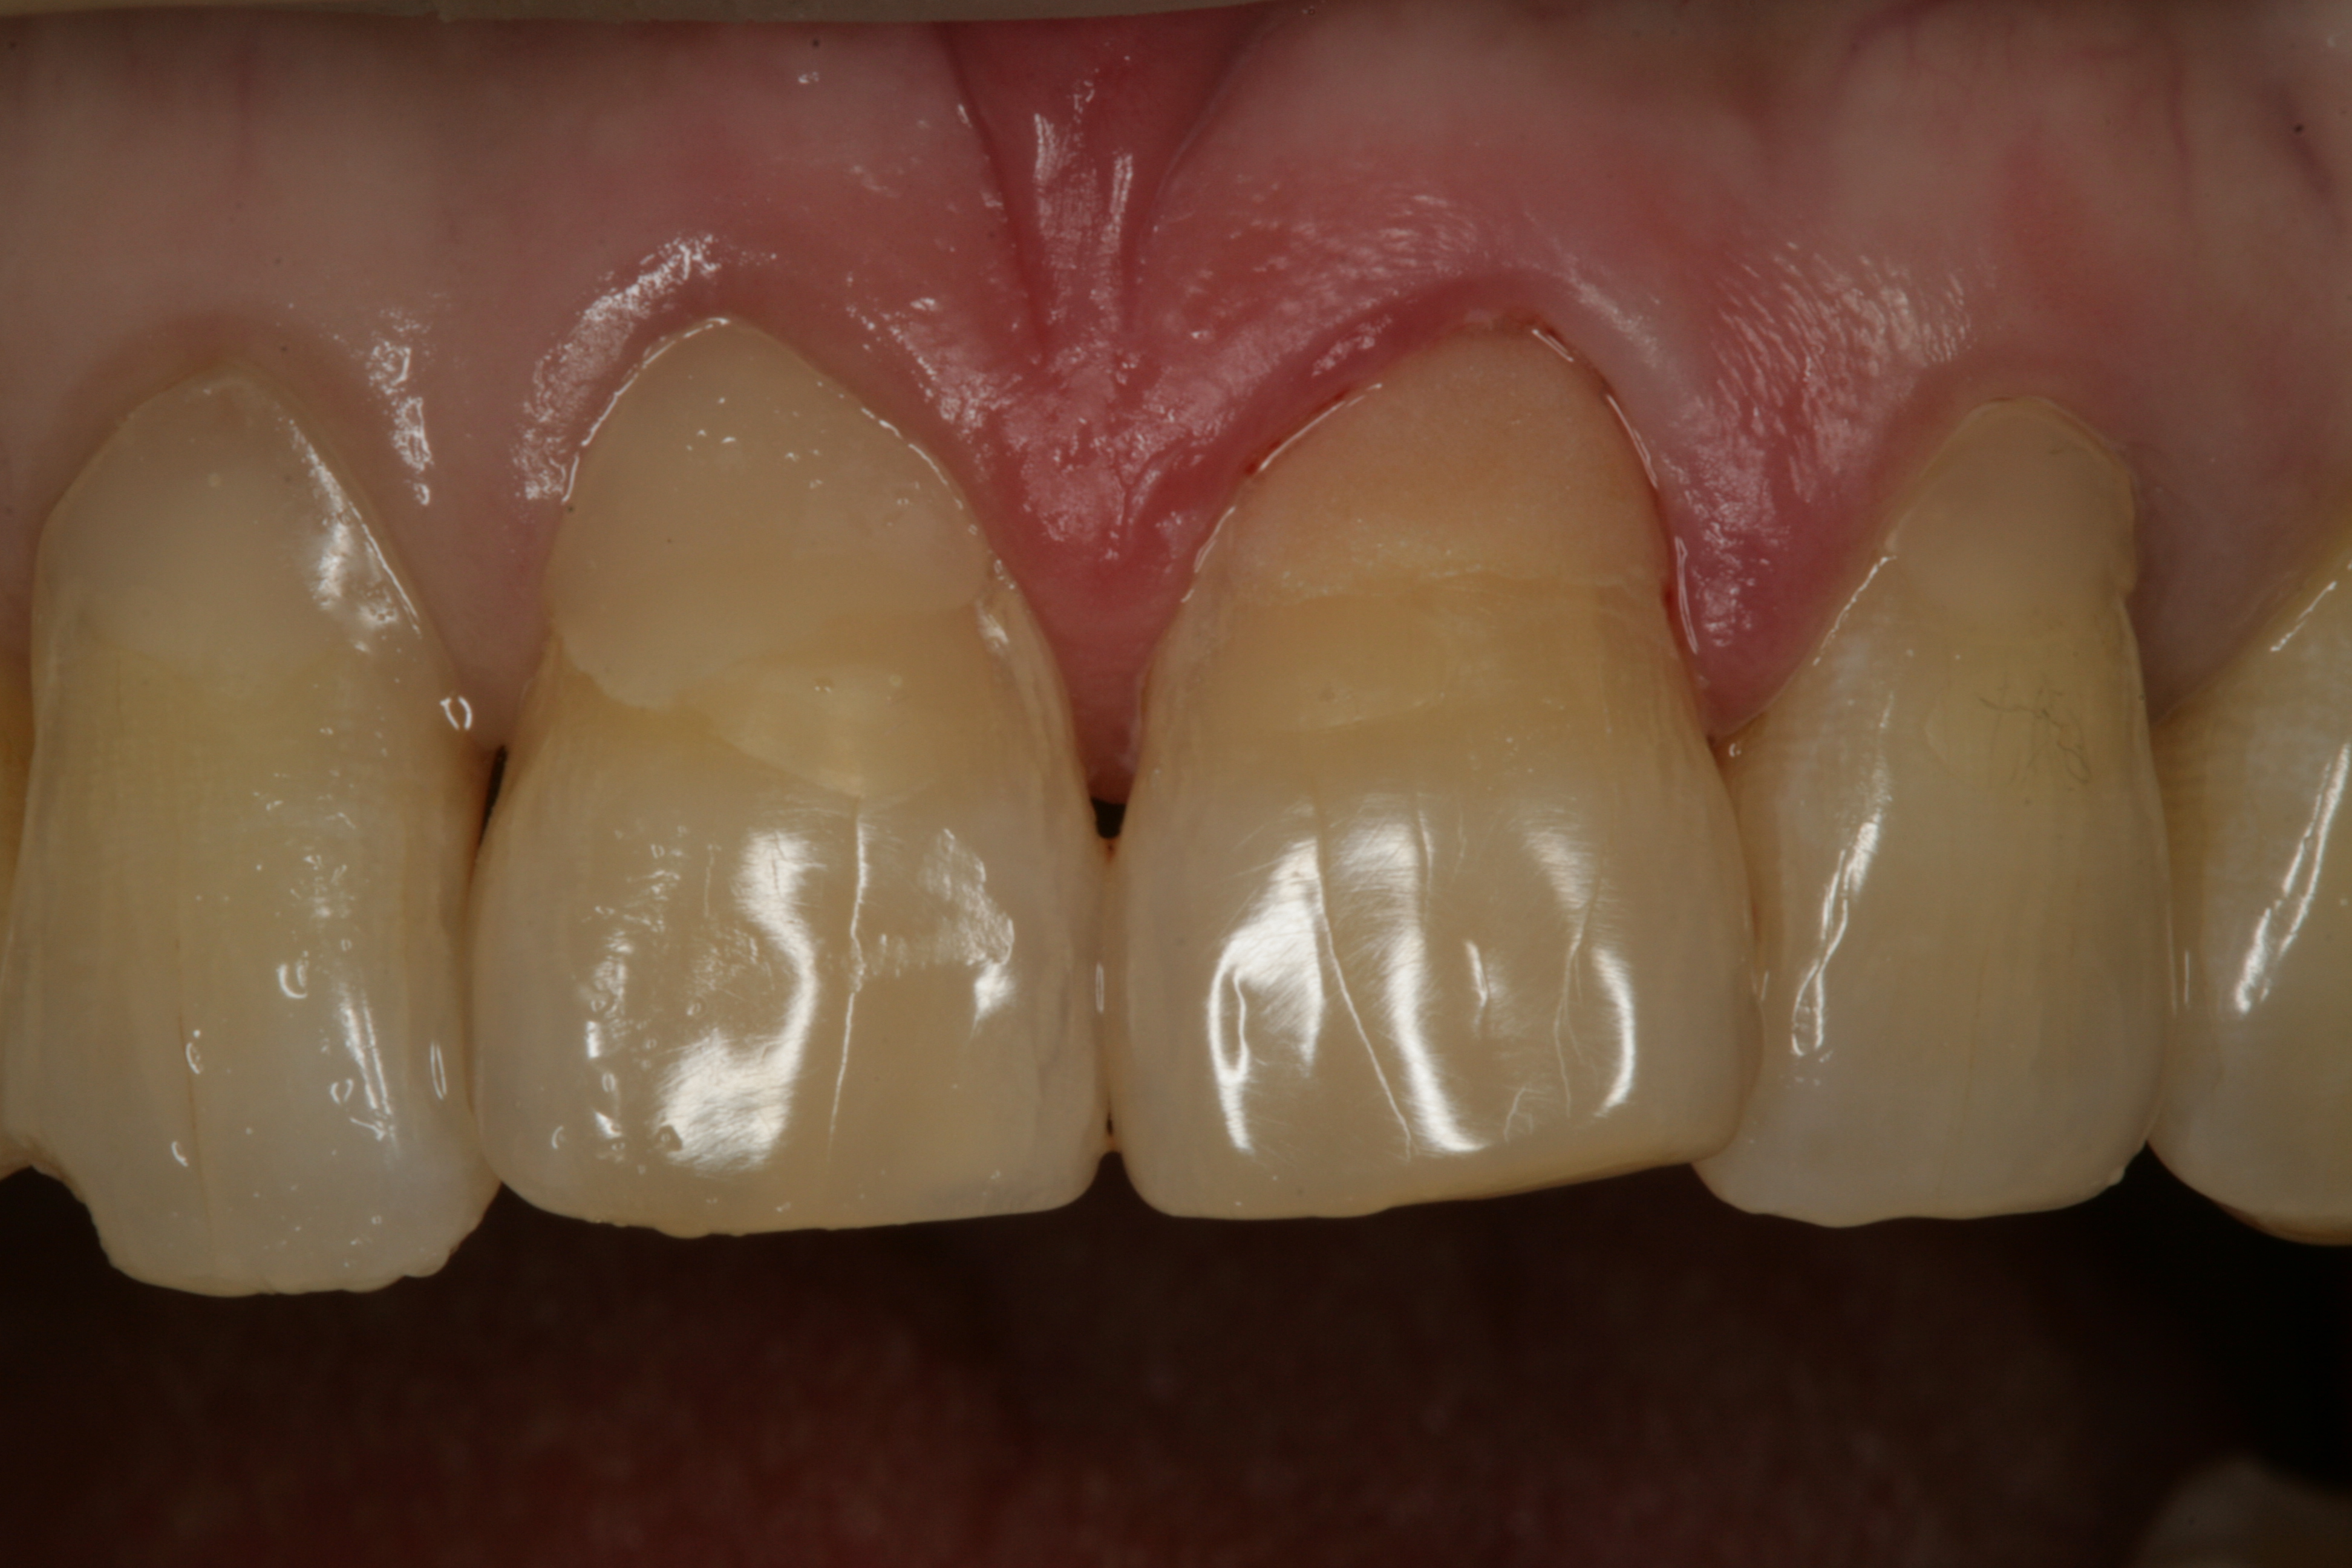

왼쪽 위 중절치가 많이 패였다며 내원하신 환자분의 임상사진입니다.

치아와 잇몸사이 부분인 치경부가 많이 패여있음을 볼 수 있습니다. 이것을 치경부 마모증이라고 합니다.

과도한 교합력, 잘못된 칫솔질 등의 원인으로 치경부 마모증이 생기게 됩니다.